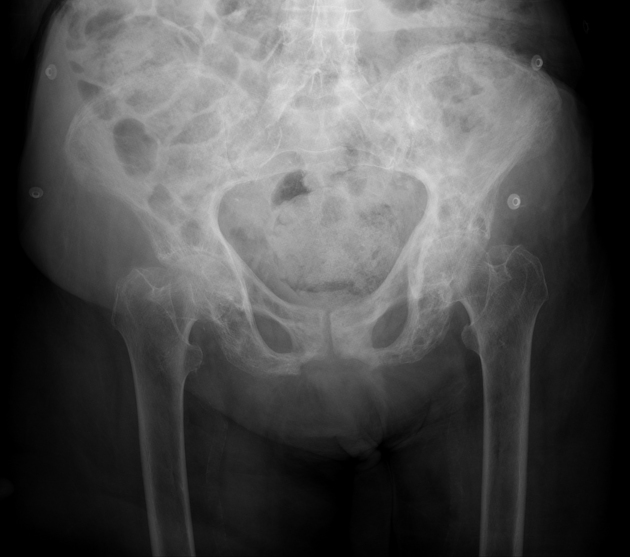

A 67-year-old man presents to the physician because of low-back pain for 6 months. The pain is more localized to the left lower back and sacral area. It is constant without any radiation to the leg. He has no significant past medical history. He takes ibuprofen for pain control. His father developed a bone disease at 60 years of age and subsequently had a fracture in the spine and another in the lower leg. The patient’s vital signs are within normal limits. The neurologic examination shows no focal findings. He has mild tenderness on deep palpation of the left pelvis. The physical examination of the lower extremities shows no abnormalities other than bowed legs. A radiograph of the pelvis is shown in the image. Which of the following serum tests is the most important initial diagnostic study?